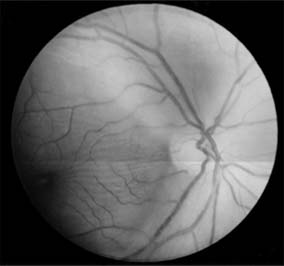

Figure 14-9

Figure 14-9: Mild papilledema. The disk margins are blurred superiorly and inferiorly by the thickened layer of nerve fibers entering the disk.